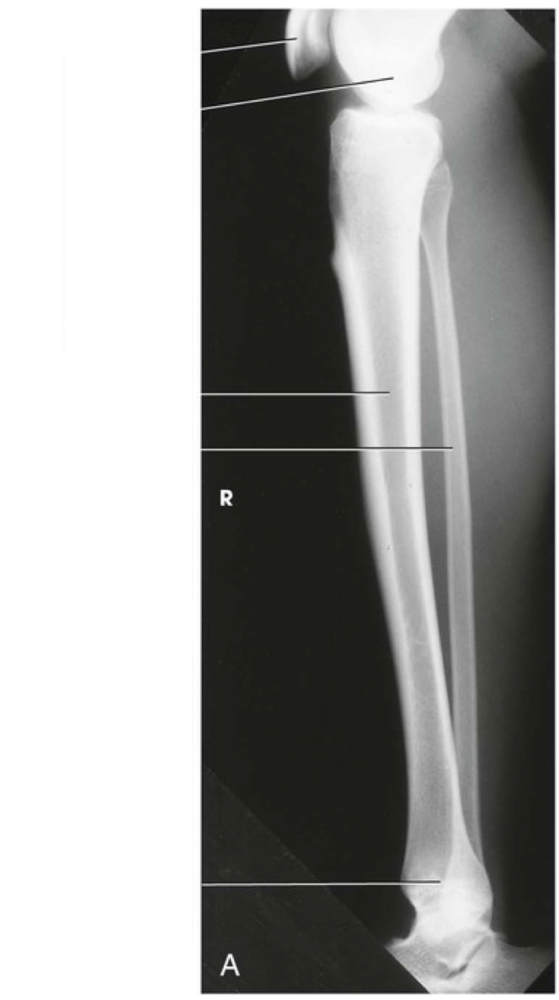

Question 4

Question

Label the image

Image:

15e1ea34-f491-43b4-b8c9-d5e76573228a (image/png)

Answer

femur

tibial plateau

tibia

fibula